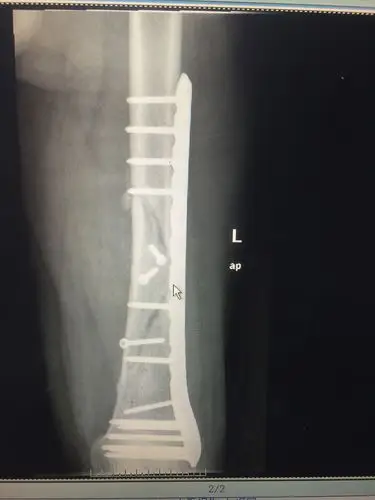

mippo微创技术治疗股骨远端骨折

求助一例股骨远端骨折

股骨远端骨折术后锁定钢板断裂

股骨远端开放性粉碎性骨折

右股骨远端开放粉碎性骨折

股骨远端骨折